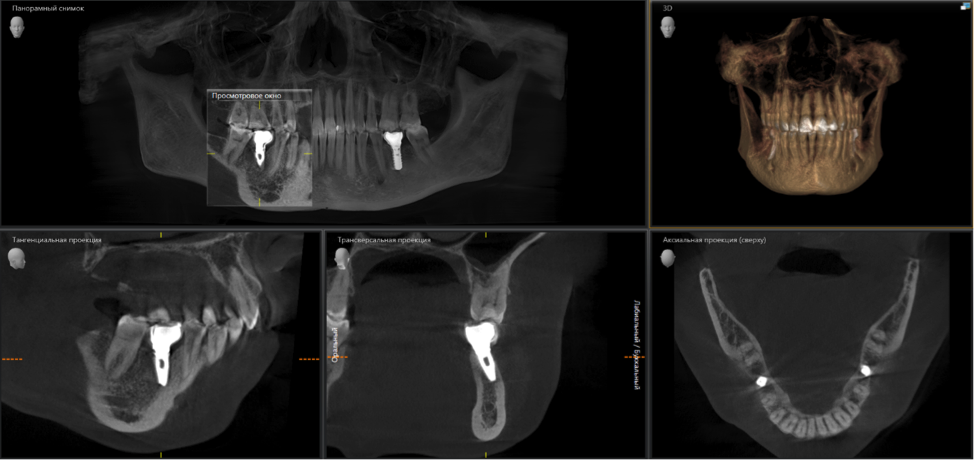

Вот фрагмент компьютерной томографии.

Имплантат стоит под серьёзным наклоном. Его ось не соответствует осям «родных» зубов. Нагрузка по принципу рычага распределяется неправильно, да и коронка имеет неправильную анатомическую форму — с нависающими краями, под которые забивается пища и зубной налет.

Развивается воспаление и, как следствие, убыль костной ткани и десны вокруг имплантата. Мало кто из вас хотел бы заплатить деньги за работу, которая в итоге пойдет по бороде. Даже индивидуальные абатменты тут не помогут.